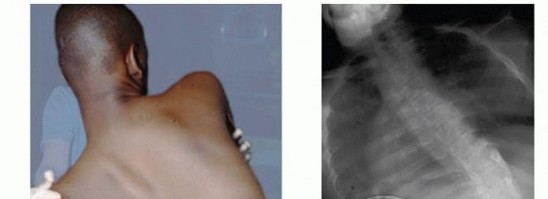

Pelvic Fixation for Neuromuscular Scoliosis DEFINITION Neuromuscular scoliosis (NMS) is a spinal deformity in…

Spinal Fusion for Neuromuscular Scoliosis DEFINITION Neuromuscular diseases are heterogeneous between and wit…